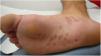

Un varón de 26 años, sin antecedentes de interés, acudió a urgencias por unas lesiones asintomáticas palmoplantares de 3 semanas de evolución, que no habían respondido al tratamiento tópico con prednicarbato, 2 veces al día, durante 20 días. Negaba fiebre u otro tipo de sintomatología sistémica. El paciente tampoco refería antecedentes de úlcera oral o genital en las últimas semanas o meses, ni relaciones sexuales de riesgo. A la exploración física se observaban unas placas ovaladas eritematosas, algunas de ellas con una descamación fina en collarete, localizadas en palmas (fig. 1), plantas y caras laterales de los pies (fig. 2). El estudio histopatológico mostró una dermatitis perivascular superficial linfocitaria, con una mínima exocitosis epidérmica asociada a una espongiosis leve (fig. 3). La inmunohistoquímica para T. pallidum fue negativa. La serología de cribado mediante inmunoanálisis de quimioluminiscencia para anticuerpos totales contra T. pallidum fue negativa en una primera determinación y repetida un mes después junto a las pruebas treponémica y no treponémica de interpretación visual (TPHA y RPR) siendo todas ellas negativas de nuevo. Las lesiones se resolvieron sin tratamiento en 4 semanas manteniéndose libre de lesiones durante el seguimiento, que finalizó a los 3 meses de la resolución de las mismas tras una nueva prueba de cribado negativa para T. pallidum. Dada la evolución, los datos clínicos, histológicos y de laboratorio se llegó al diagnóstico de pitiriasis rosada (PR) atípica palmoplantar.